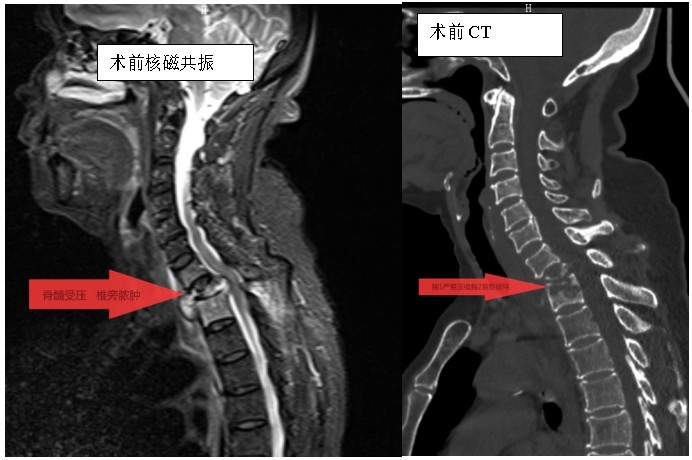

家住耒陽的70歲的李奶奶,因“頸胸背部疼痛不適伴雙上肢麻木6個(gè)月”,來到衡陽市中心醫(yī)院脊柱外科住院,住院當(dāng)天,患者頸胸椎核磁共振顯示:胸1、2椎體骨質(zhì)破壞,伴胸1、2椎旁軟組織腫脹、同層面椎管變窄,因脊髓受壓而導(dǎo)致頸胸背部疼痛。在錢軍博士帶領(lǐng)下,醫(yī)療團(tuán)隊(duì)詳細(xì)予以完善相關(guān)檢查后,研究患者的臨床資料,考慮脊柱結(jié)核并椎旁膿腫的可能性大,由于患者胸1椎體病理性骨折并椎管狹窄,遂囑患者嚴(yán)格臥床休息,術(shù)前給予標(biāo)準(zhǔn)四聯(lián)抗結(jié)核藥物治療2周,以控制活動(dòng)性結(jié)核感染,降低術(shù)中播散風(fēng)險(xiǎn),并嚴(yán)密監(jiān)測(cè)肝腎功能及血常規(guī)情況。